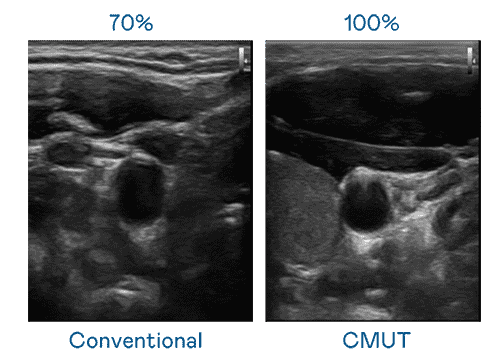

CMUT 技术是一种用电容式微机电元件来产生超音波讯号的技术。。。与传统 PZT 压电式技术相比,,,,CMUT 频宽增加 30%,,,更宽频的超音波讯号让影像解析度大幅提升,,,,是实现高影像品质医疗超音波扫描、、、促进精准医疗发展的关键技术。。。

大频宽带来超清晰影像

超音波影像的解析度高低,,首先取决于探头能发出的讯号频宽。。。PA直营 CMUT 可提供高清晰的超音波讯号,,,,提供高频宽、、、高灵敏度、、影像纹理细节更高的超音波影像,,,协助医护人员缩短影像判读时间及利用精准的医疗影像进行诊断。。。